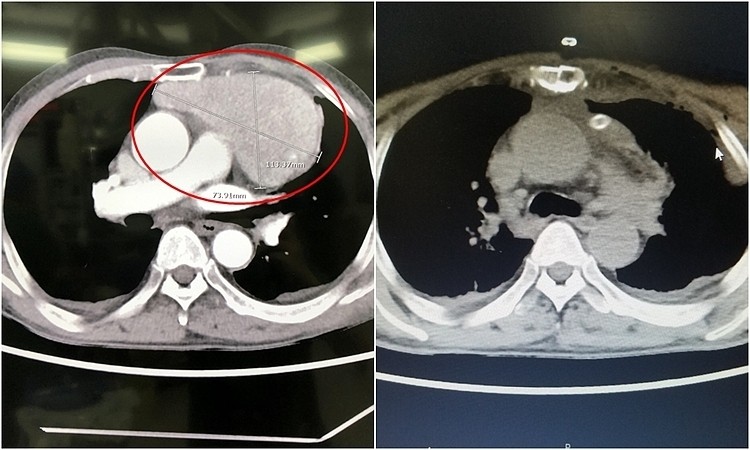

Các bác sĩ Bệnh viện Đa khoa Quảng Ninh ngày 1/7 cho biết, kết quả chẩn đoán bệnh nhân có khối u nằm ngay trước tim, kích thước lớn bằng quả tim thật, đè đẩy các mạch máu, tim và khí phế quản.

Kíp mổ tiến hành phẫu thuật theo đường mở xương ức và ngực trái bộc lộ khối u trung thất lớn, kích thước lớn, chiều dài nhất dài 11 cm, hai chiều còn lại dài 7 cm. Sau hơn 2 giờ, phẫu thuật viên bóc tách, lấy trọn khối u và tổ chức xung quanh, bảo tồn nguyên vẹn tim, các mạch máu thần kinh quan trọng vùng tim như tĩnh mạch chủ trên, động mạch chủ, động mạch phổi, thần kinh hoành, thần kinh X.